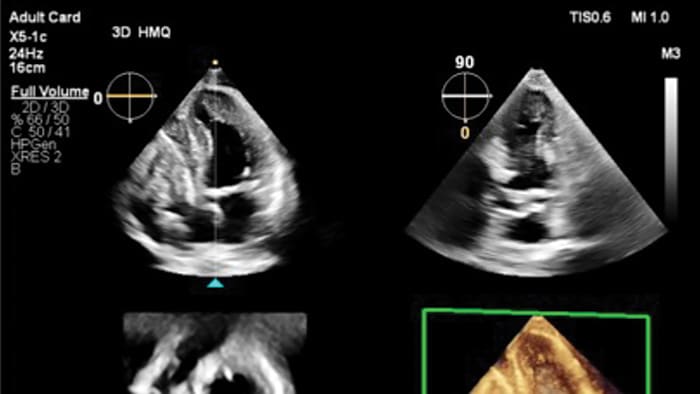

Transcend Plus mejora visiblemente la nitidez, el contraste y el detalle en las imágenes 2D y 3D, con las últimas mejoras aprobadas por la FDA para EPIQ CVx y Affiniti CVx. Estas actualizaciones respaldan una visualización superior de la anatomía y la función cardíacas, lo que permite la confianza en el diagnóstico incluso en los casos más complejos o técnicamente desafiantes. La actualización también presenta la nueva función 2D Auto EF Advanced, que amplía las capacidades de IA para imágenes de contraste, esenciales para evaluar con precisión la función cardíaca.

Transcend Plus permite a los médicos tomar decisiones rápidas y seguras en todos los entornos de atención cardíaca, ya sea en el laboratorio de ecocardiografía, en la sala de intervención o durante las evaluaciones ambulatorias de rutina. Al ofrecer imágenes más nítidas y automatización inteligente, permite una atención más informada, agiliza los flujos de trabajo y ayuda a los proveedores a administrar volúmenes crecientes de pacientes sin comprometer la calidad del diagnóstico o el bienestar del médico. Transcend Plus ofrece tres beneficios principales: calidad de imagen mejorada para una visualización más clara de la anatomía cardíaca y precisión diagnóstica mejorada; integración avanzada de IA, con 26 aplicaciones aprobadas por la FDA que automatizan y aceleran las tareas rutinarias; y conocimientos más rápidos y procesables que reducen las demoras y respaldan las decisiones clínicas oportunas y basadas en evidencia a lo largo del proceso de atención.